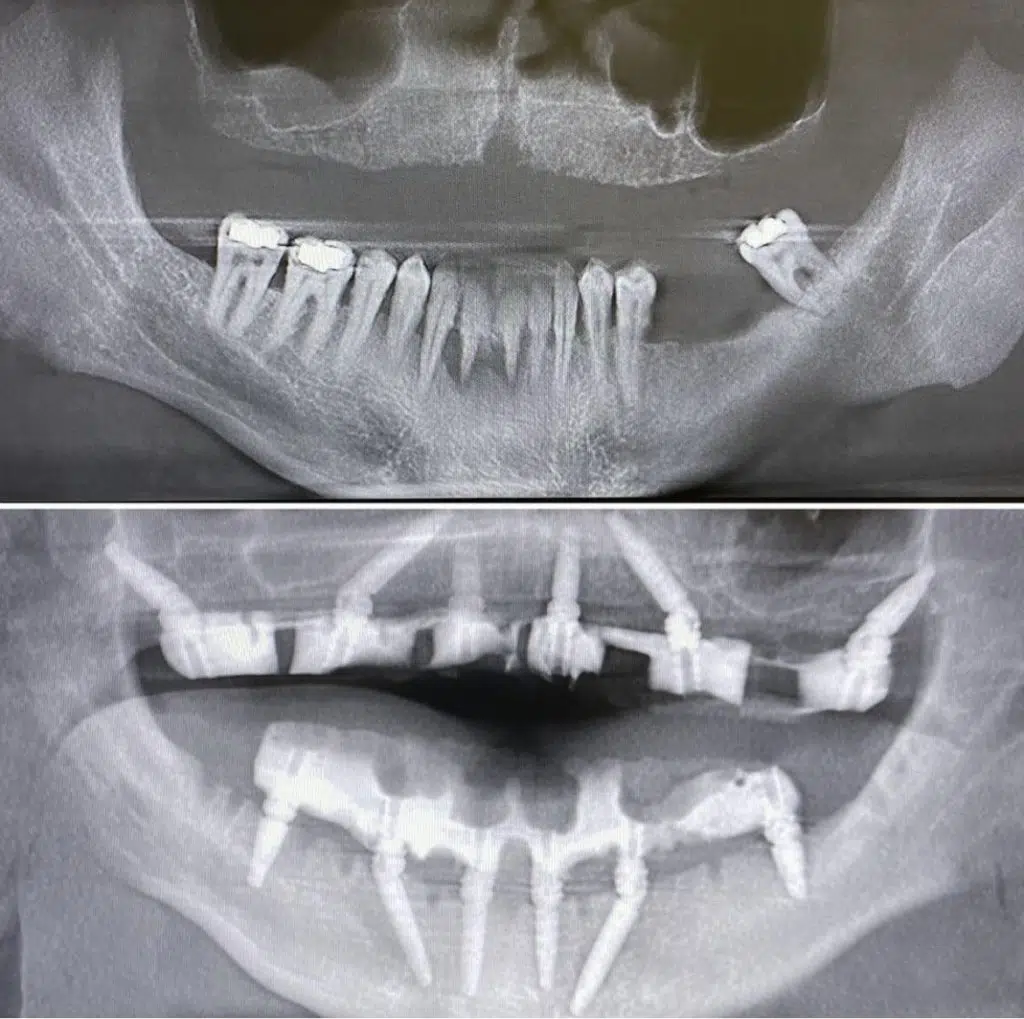

Dental implant surgery is constantly evolving, with literature supporting many of the advancements proposed in the mid-1990s. One of these advancements is extracting all remaining teeth, placing 4-6 implants, and immediately providing a screwed-down temporary prosthesis – the all on 4 protocol.

There have been thousands of all on 4 completed cases throughout the world. In fact, Dr. Damon has personally completed over 1,000 all on four cases as of 2020. Let alone the number of thousands of other single unit implants or “snap-on” dental implants that he has also completed.